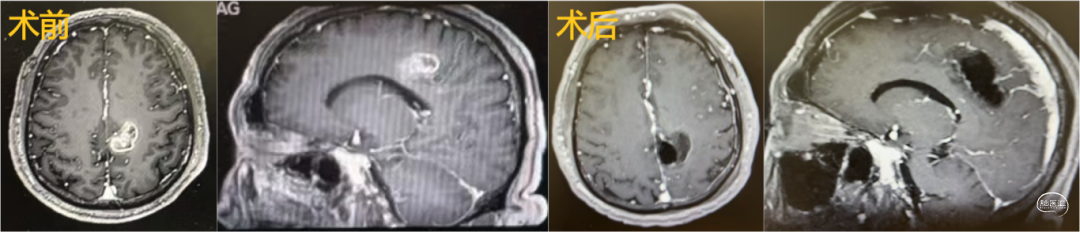

3.运动区肿瘤切除术